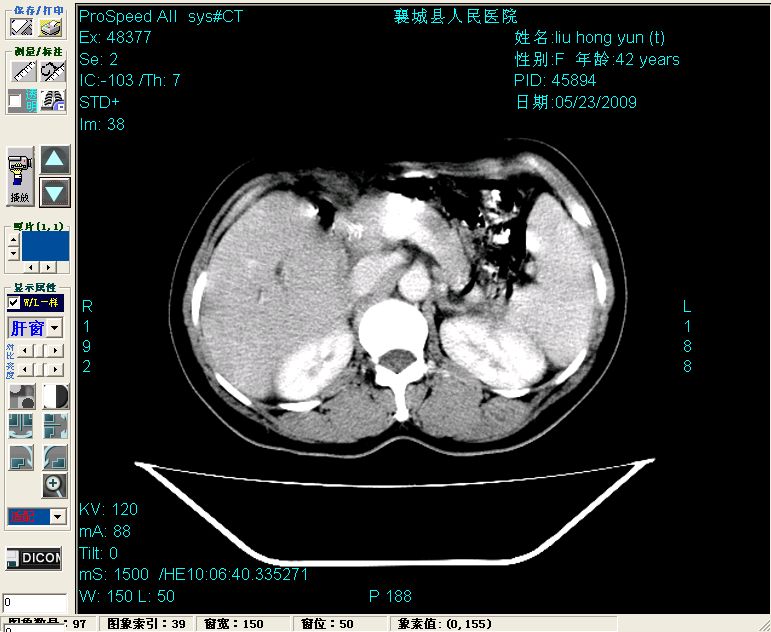

增强:

增强动脉期前述低密度区轻度早其强化,门脉期强化程度显著增高,延期扫描强化程度下降,但仍为相对高密度影

胰头部见结节状高密度影,其前方略可分辨扩强胆部管,平扫到增强始终有,但现在尚难与胃肠造影剂鉴别.

结合病史考虑,1现在引起黄疸体征的原因应该是胆总管胰段结石阻塞,建议局部胃肠造影剂排空后复查.

2左肝及右肝前叶表现考虑胆囊摘除术后所致的肝动门脉瘘形成,慢性纤维组织炎性增生.不完全除外左肝胆管细胞癌

考虑:1、胆道结石伴肝内胆管扩张、积气;胆系感染!2、从平扫、增强片来看,不存在胆管肿瘤征象;3、提介建议:作为影像医师,在做一项检查之前应先熟悉临床医生的目的,象这个病例,检查前就不应喝高密度造影剂,而应充分喝好水就可,要不适得其反,反而较难判断胆总管下段是否有结石。

1)肝内胆管结石,胆总管末端结石伴肝内胆管扩张。2)肝左叶及肝右叶前段增强前后之异常表现,考虑炎性改变,不排除胆管细胞癌。